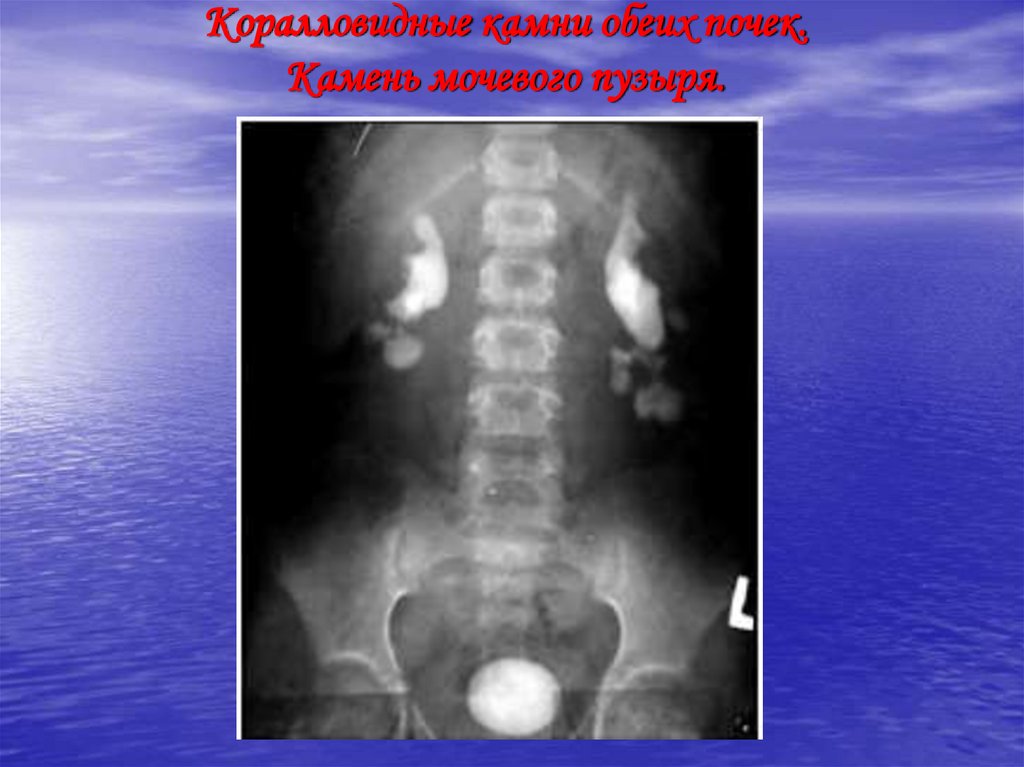

Коралловидные камни обеих почек. Камень мочевого пузыря.

39. Коралловидные камни обеих почек. Камень мочевого пузыря.